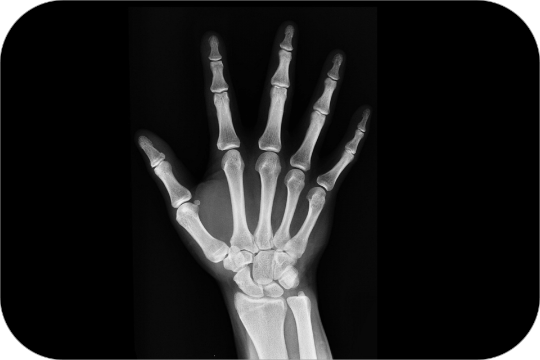

Carpal